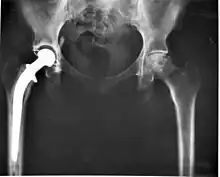

The modern total hip replacement was pioneered by Sir John Charnley, expert in tribology at Wrightington Hospital, in England in the 1960s.[10] He found that joint surfaces could be replaced by implants cemented to the bone. His design consisted of a stainless steel, one-piece femoral stem and head, and a polyethylene acetabular component, both of which were fixed to the bone using PMMA (acrylic) bone cement. For over two decades, the Charnley low-friction arthroplasty and its derivative designs were the most-used systems in the world. This formed the basis for all modern hip implants.

The Exeter hip replacement system (with a slightly different stem geometry) was developed at the same time. Since Charnley, improvements have been continuous in the design and technique of joint replacement (arthroplasty) with many contributors, including W. H. Harris, the son of R. I. Harris, whose team at Harvard pioneered uncemented arthroplasty techniques with the bone bonding directly to the implant.

Arthroplasty is an orthopedic surgery where the articular surface of a musculoskeletal joint is replaced, remodeled, or realigned by osteotomy or some other procedure. It is an elective procedure that is done to relieve pain and restore function to the joint after damage by arthritis (rheumasurgery) or some other type of trauma. As well as the standard total knee replacement surgery, the uni-compartmental knee replacement, in which only one weight-bearing surface of an arthritic knee is replaced, is a popular alternative.[27]

Joint replacements are available for other joints on a variable basis, most notably the hip, shoulder, elbow, wrist, ankle, spine, and finger joints.

In recent years, surface replacement of joints, in particular the hip joint, has become more popular amongst younger and more active patients.[28] This type of operation delays the need for the more traditional and less bone-conserving total hip replacement, but carries significant risks of early failure from fracture and bone death.